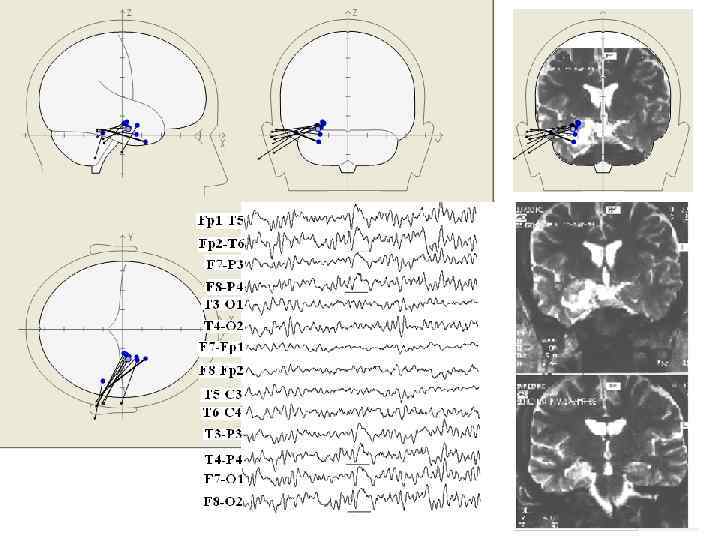

Симптоматическая фронто-полярная лобнодолевая эпилепсия - Карбамазепин 800 мг

Симптоматичесская фронто-полярная лобнодолевая эпилепсия

• • Эпилептический синдром нарушения развития правого полушария у девочки 8 лет В раннем детстве - пирамидная недостаточность левой ноги Единичный генерализованный эпилептический тоникоклонический припадок Жалобы: Выраженная замедленность, нарушение счетных операций, дизлексия, нарушение внимания, неспособность участвовать в коллективной деятельности, трудности ориентации в пространстве, эмоциональные нарушения. Нейропсихологическое исследование: снижение общей и, особенно, зрительной памяти, дисклькулия, визуопространственный когнитивный дефицит.

Синдром нарушения развития правого полушария